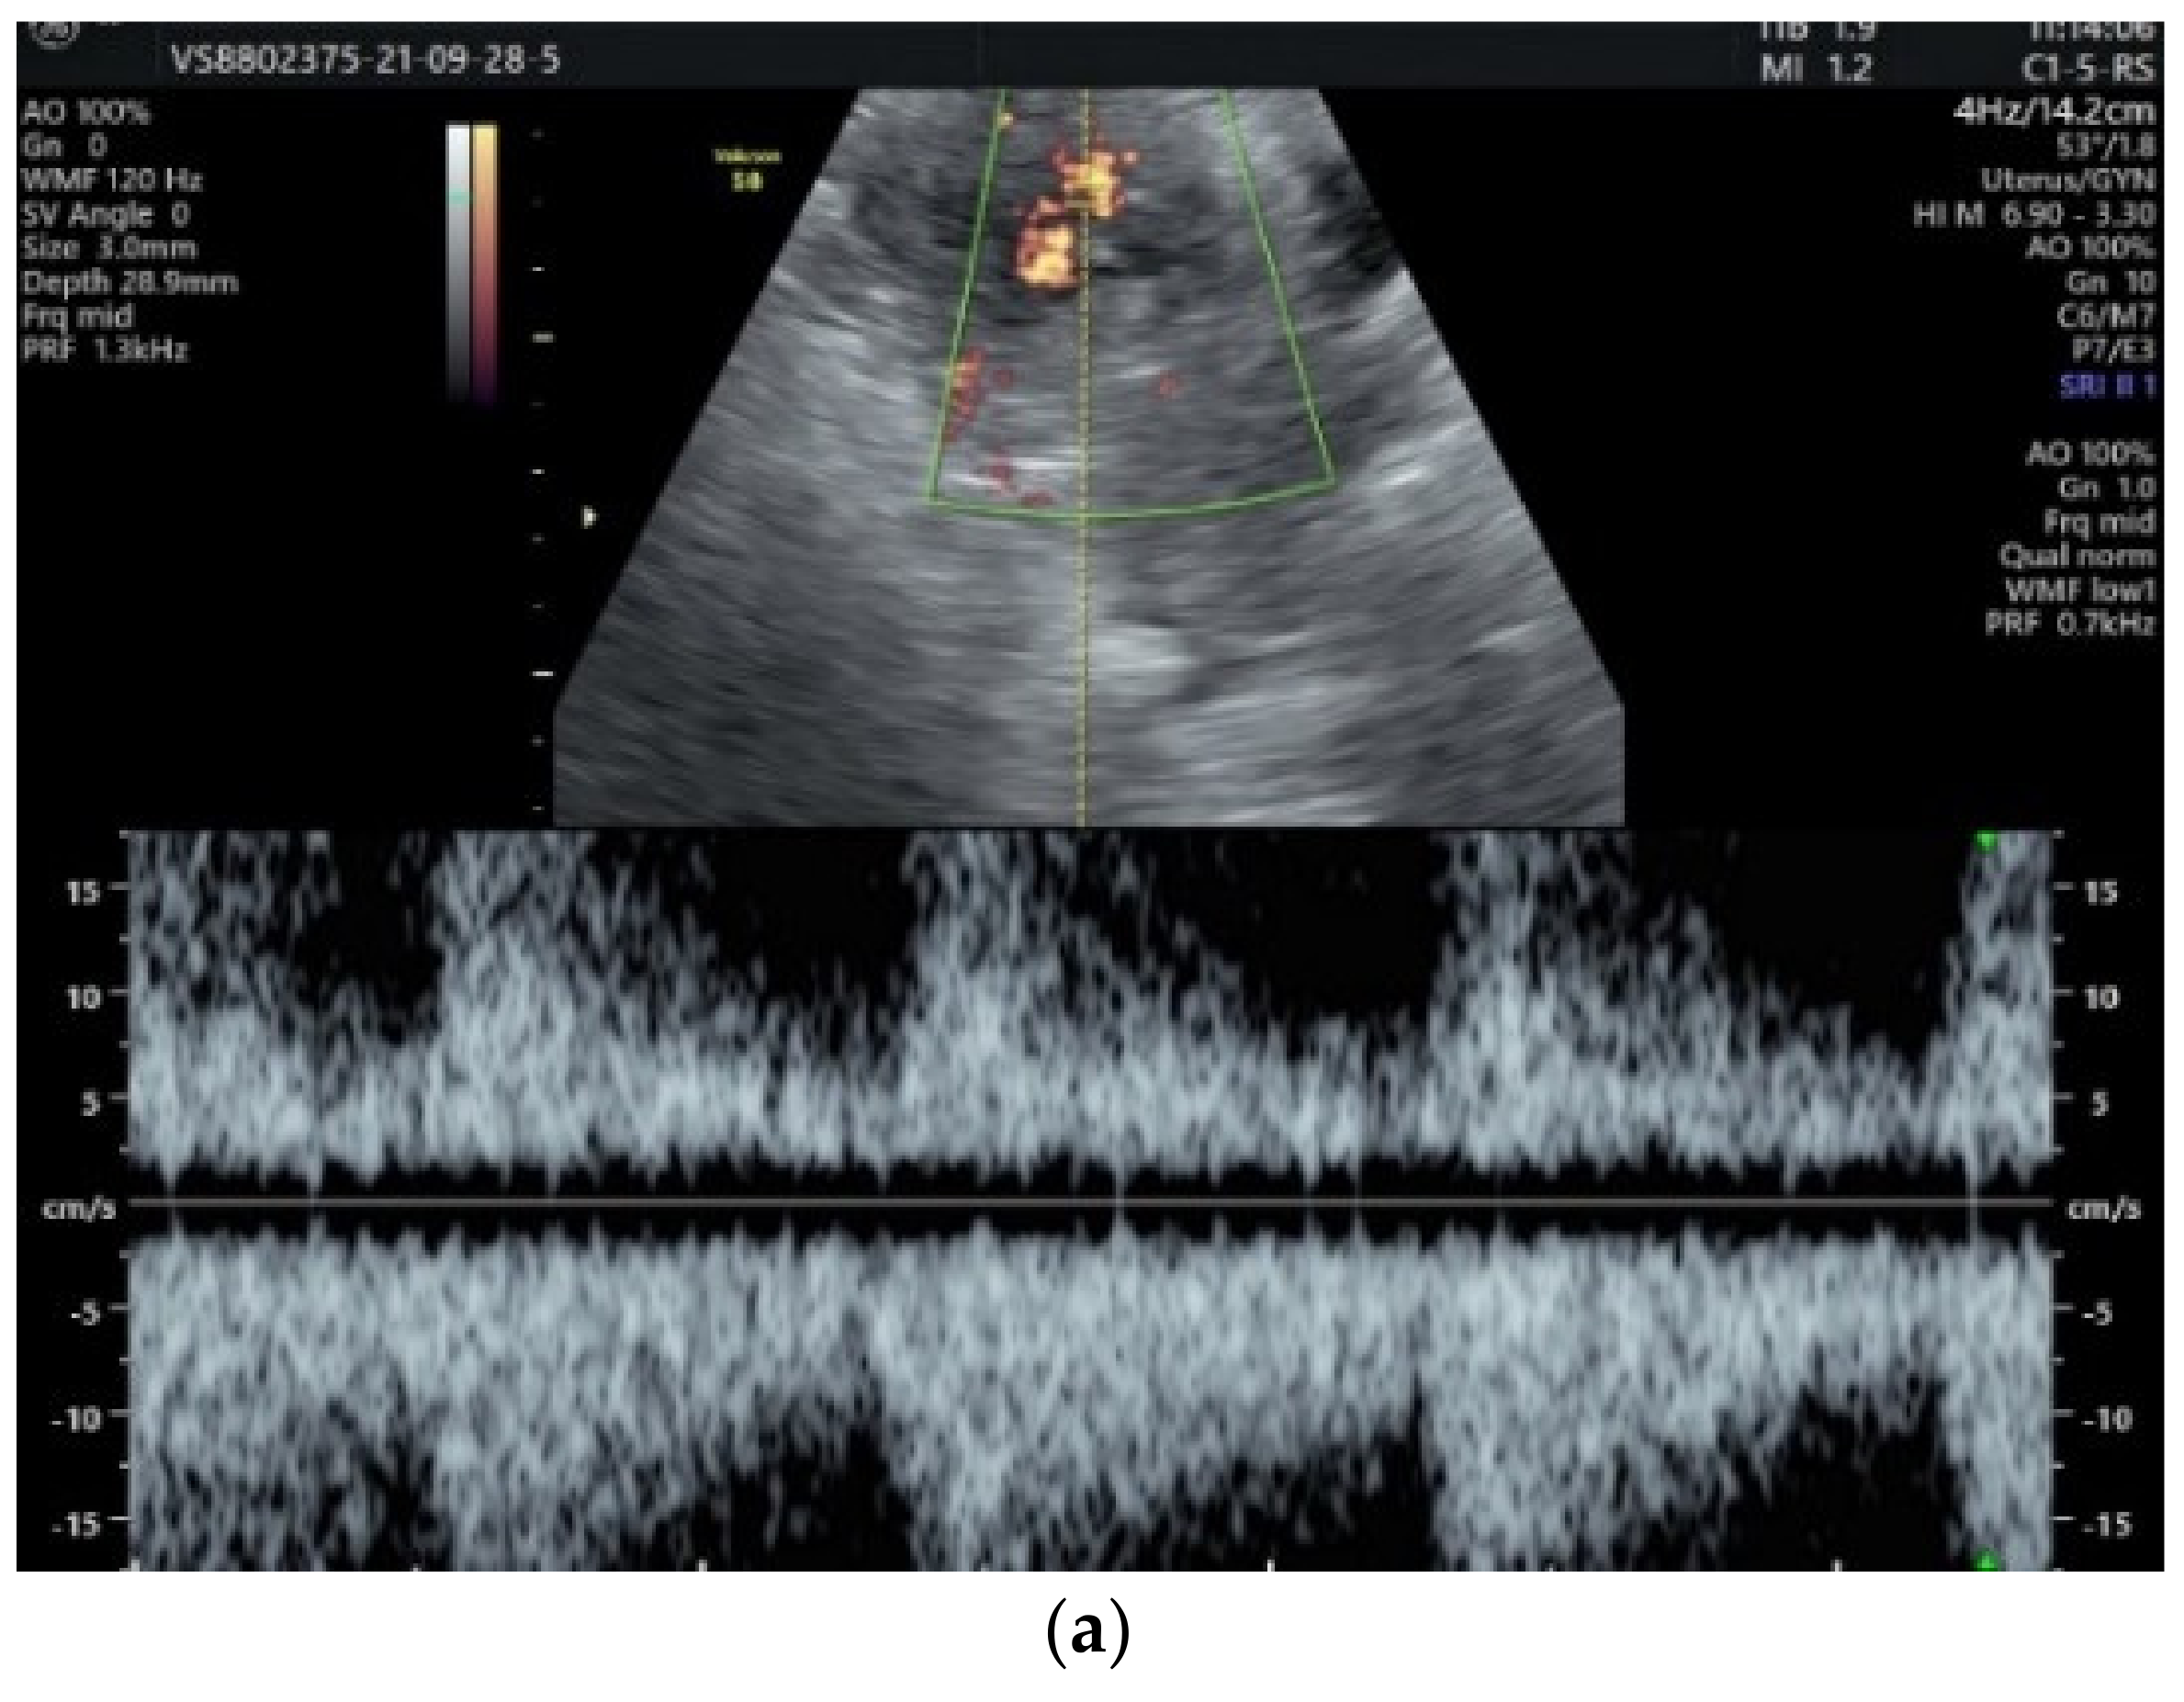

2. Case Presentation